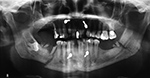

Numbering of the teeth is important for consistent description of dental anatomy. The American Dental Association recognizes two major systems for numbering the teeth. The Universal/National System is used primarily in the United States, and the International Standards Organization System (ISO) is used in most other countries. The Universal/National System for permanent dentition numbers teeth beginning with the right maxillary third molar labeled as tooth number 1, following around the maxillary arch to the left maxillary third molar, descending to the left mandibular third molar, and following around the mandibular arch to the right mandibular third molar labeled tooth number 32 (figure: tooth numbering).

| Tooth Numbering |

| The Universal/National System for permanent dentition numbers teeth beginning with the right maxillary third molar labeled as tooth number 1, following around the maxillary arch to the left maxillary third molar, descending to the left mandibular third molar, and following around the mandibular arch to the right mandibular third molar labeled tooth number 32.